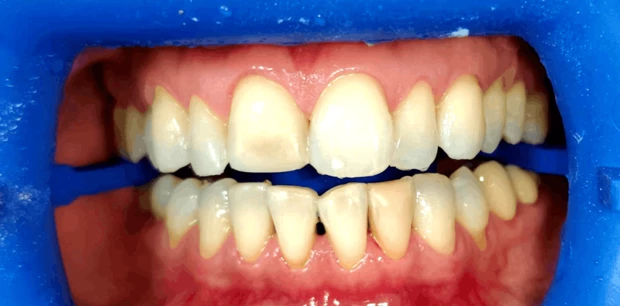

Ортодонтия

Ортодонтическое лечение элайнерами

Пациент И., 10 лет. Родители обратились с жалобами на неровные зубы сына. Проведено ортодонтическое лечение элайнерами. Лечение проводилось 1,5 года.